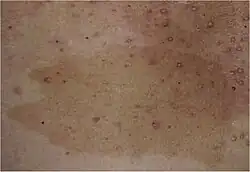

Etwa 50 Prozent der betroffenen Personen haben eine Neumutation. NF1 betrifft vor allem Haut und Nervensystem. Sie wird daher den neurokutanen Erkrankungen (Phakomatosen) zugeordnet. Typische Veränderungen an der Haut sind Café-au-lait-Flecken sowie Neurofibrome. Als Café-au-lait-Flecken bezeichnet man milchkaffeefarbene Hyperpigmentierungen der Haut. Sie liegen im Niveau der Haut, können bei allen Menschen auftreten und sind harmlos. Bei Menschen mit einer NF1 treten sie gehäuft auf. Als Neurofibrome bezeichnet man gutartige Tumoren, die von den Zellen der Schwann’schen Scheiden kleiner Nervenfasern in der Haut ausgehen. Im zentralen Nervensystem (ZNS) treten gehäuft Tumoren verschiedener Lokalisation auf. Patienten können aufgrund der Erkrankung geistig behindert (minderbegabt) sein und an epileptischen Anfällen leiden. Des Weiteren sind häufig Augen (mit resultierender Sehschwäche) und Knochen mitbetroffen. Die Pubertät kann verfrüht oder verspätet eintreten. Eine Neurofibromatose wird durch eine Veränderung in einem Gen hervorgerufen, welches normalerweise hemmend auf die Zellteilung Einfluss nimmt. Es kommt daher zu überschießender Gewebsvermehrung und damit zu den typischen Veränderungen. Die Diagnose wird meist anhand des klinischen Bildes bereits in der Kindheit gestellt. Da es sich bei Morbus Recklinghausen um eine genetische Erkrankung handelt, ist eine Therapie, welche ihre Ursache beseitigt, derzeit nicht möglich. Es werden daher nur Veränderungen behandelt, die für den Patienten störend oder gefährlich sind. Eine weitere bekannte Form der Neurofibromatose ist die Neurofibromatose Typ 2 (NF2), welche wesentlich seltener auftritt und von einer Mutation auf einem anderen Gen verursacht wird.

Café-au-lait-Flecken, Freckling im Bereich beider Achselhöhlen (sogenanntes Axillary Freckling) und Lisch-Knötchen gehen auf Veränderungen der Melanozyten der Haut zurück. Dabei sind Café-au-lait-Flecken oft schon bei der Geburt vorhanden und werden im Lauf der Kindheit häufiger und größer. Freckling, eine Art Sommersprossenbildung im Bereich der Achselhöhlen und der Oberkörperseiten, tritt meist ab einem Alter von etwa 5–7 Jahre auf. Lisch-Knötchen treten oft erst während oder nach der Pubertät auf. Histologisch ist das Verhältnis von Melanozyten zu Keratinozyten, das bei der Neurofibromatose Typ 1 bereits in der nicht betroffenen Haut verschoben ist, im Bereich von Café-au-Lait-Flecken und Freckling weiter erhöht. Bei den im Bereich der Iris des Auges auftretenden Lisch-Knötchen handelt es sich histologisch um kleine pigmentierte Hamartome.

Café-au-lait-Flecken und Farbveränderungen der Achsel sind auffällige Hauterscheinungen. In mehr als 95 Prozent der Fälle finden sich Café-au-lait-Flecken bei Patienten mit der Neurofibromatose Recklinghausen.[11] Etwa 80 Prozent weisen mehr als sechs große hyperpigmentierte Areale auf. Allerdings kommen Café-au-lait-Flecken auch bei etwa zehn Prozent der nicht betroffenen Bevölkerung vor. Es handelt sich bei dieser Veränderung um große (bis zu mehreren Zentimetern), scharf und unregelmäßig begrenzte hell- bis dunkelbraune Flecken, die oft schon bei Geburt oder in der Kindheit auffallen. Sie sind am Körper ohne erkennbare Ordnung verteilt. Es liegt eine Vermehrung von Melanozyten vor.

Das sogenannte Freckling (engl. freckle = Sommersprossen, Tüpfel, Sprenkel) ist eine sommersprossenähnliche Verfärbung an Körperstellen, die normalerweise keiner Sonnenbestrahlung ausgesetzt sind. Am auffälligsten sind diese Veränderungen in der Achselhöhle und Leistenregion. Dies wird ab einem Alter von etwa 10 Jahren beobachtet. Da in etwa 90 Prozent das Freckling bei Patienten mit Neurofibromatose Typ 1 auftritt, ist es eine diagnostisch wegweisende Erscheinung. Daneben werden auch diffuse Farbveränderungen des Rumpfes (Lentiginose) beschrieben, die ebenso gehäuft im Bereich der Axillen auftreten.